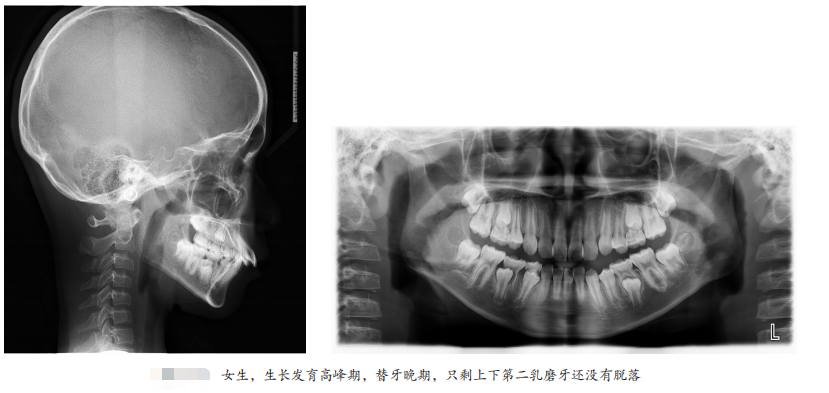

一般在替牙中期孩子上下4颗门牙换完,是比较好的干预时机,再就是女孩替牙晚期,只剩上下第二乳磨牙还没有脱落;男孩刚刚结束替牙期,正处于年轻恒牙列阶段,还有机会引导下颌向前生长。